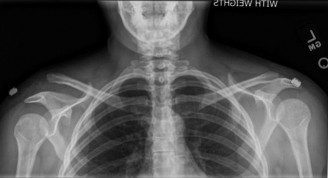

A 17-year-old, football player with a history of multiple, left shoulder dislocations and an attempted arthro…